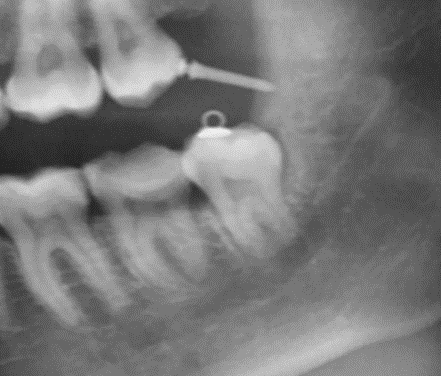

Так мы поступаем с восьмыми зубами, которые нужно удалять очень аккуратно, если через их корни проходит нерв, вот пример: